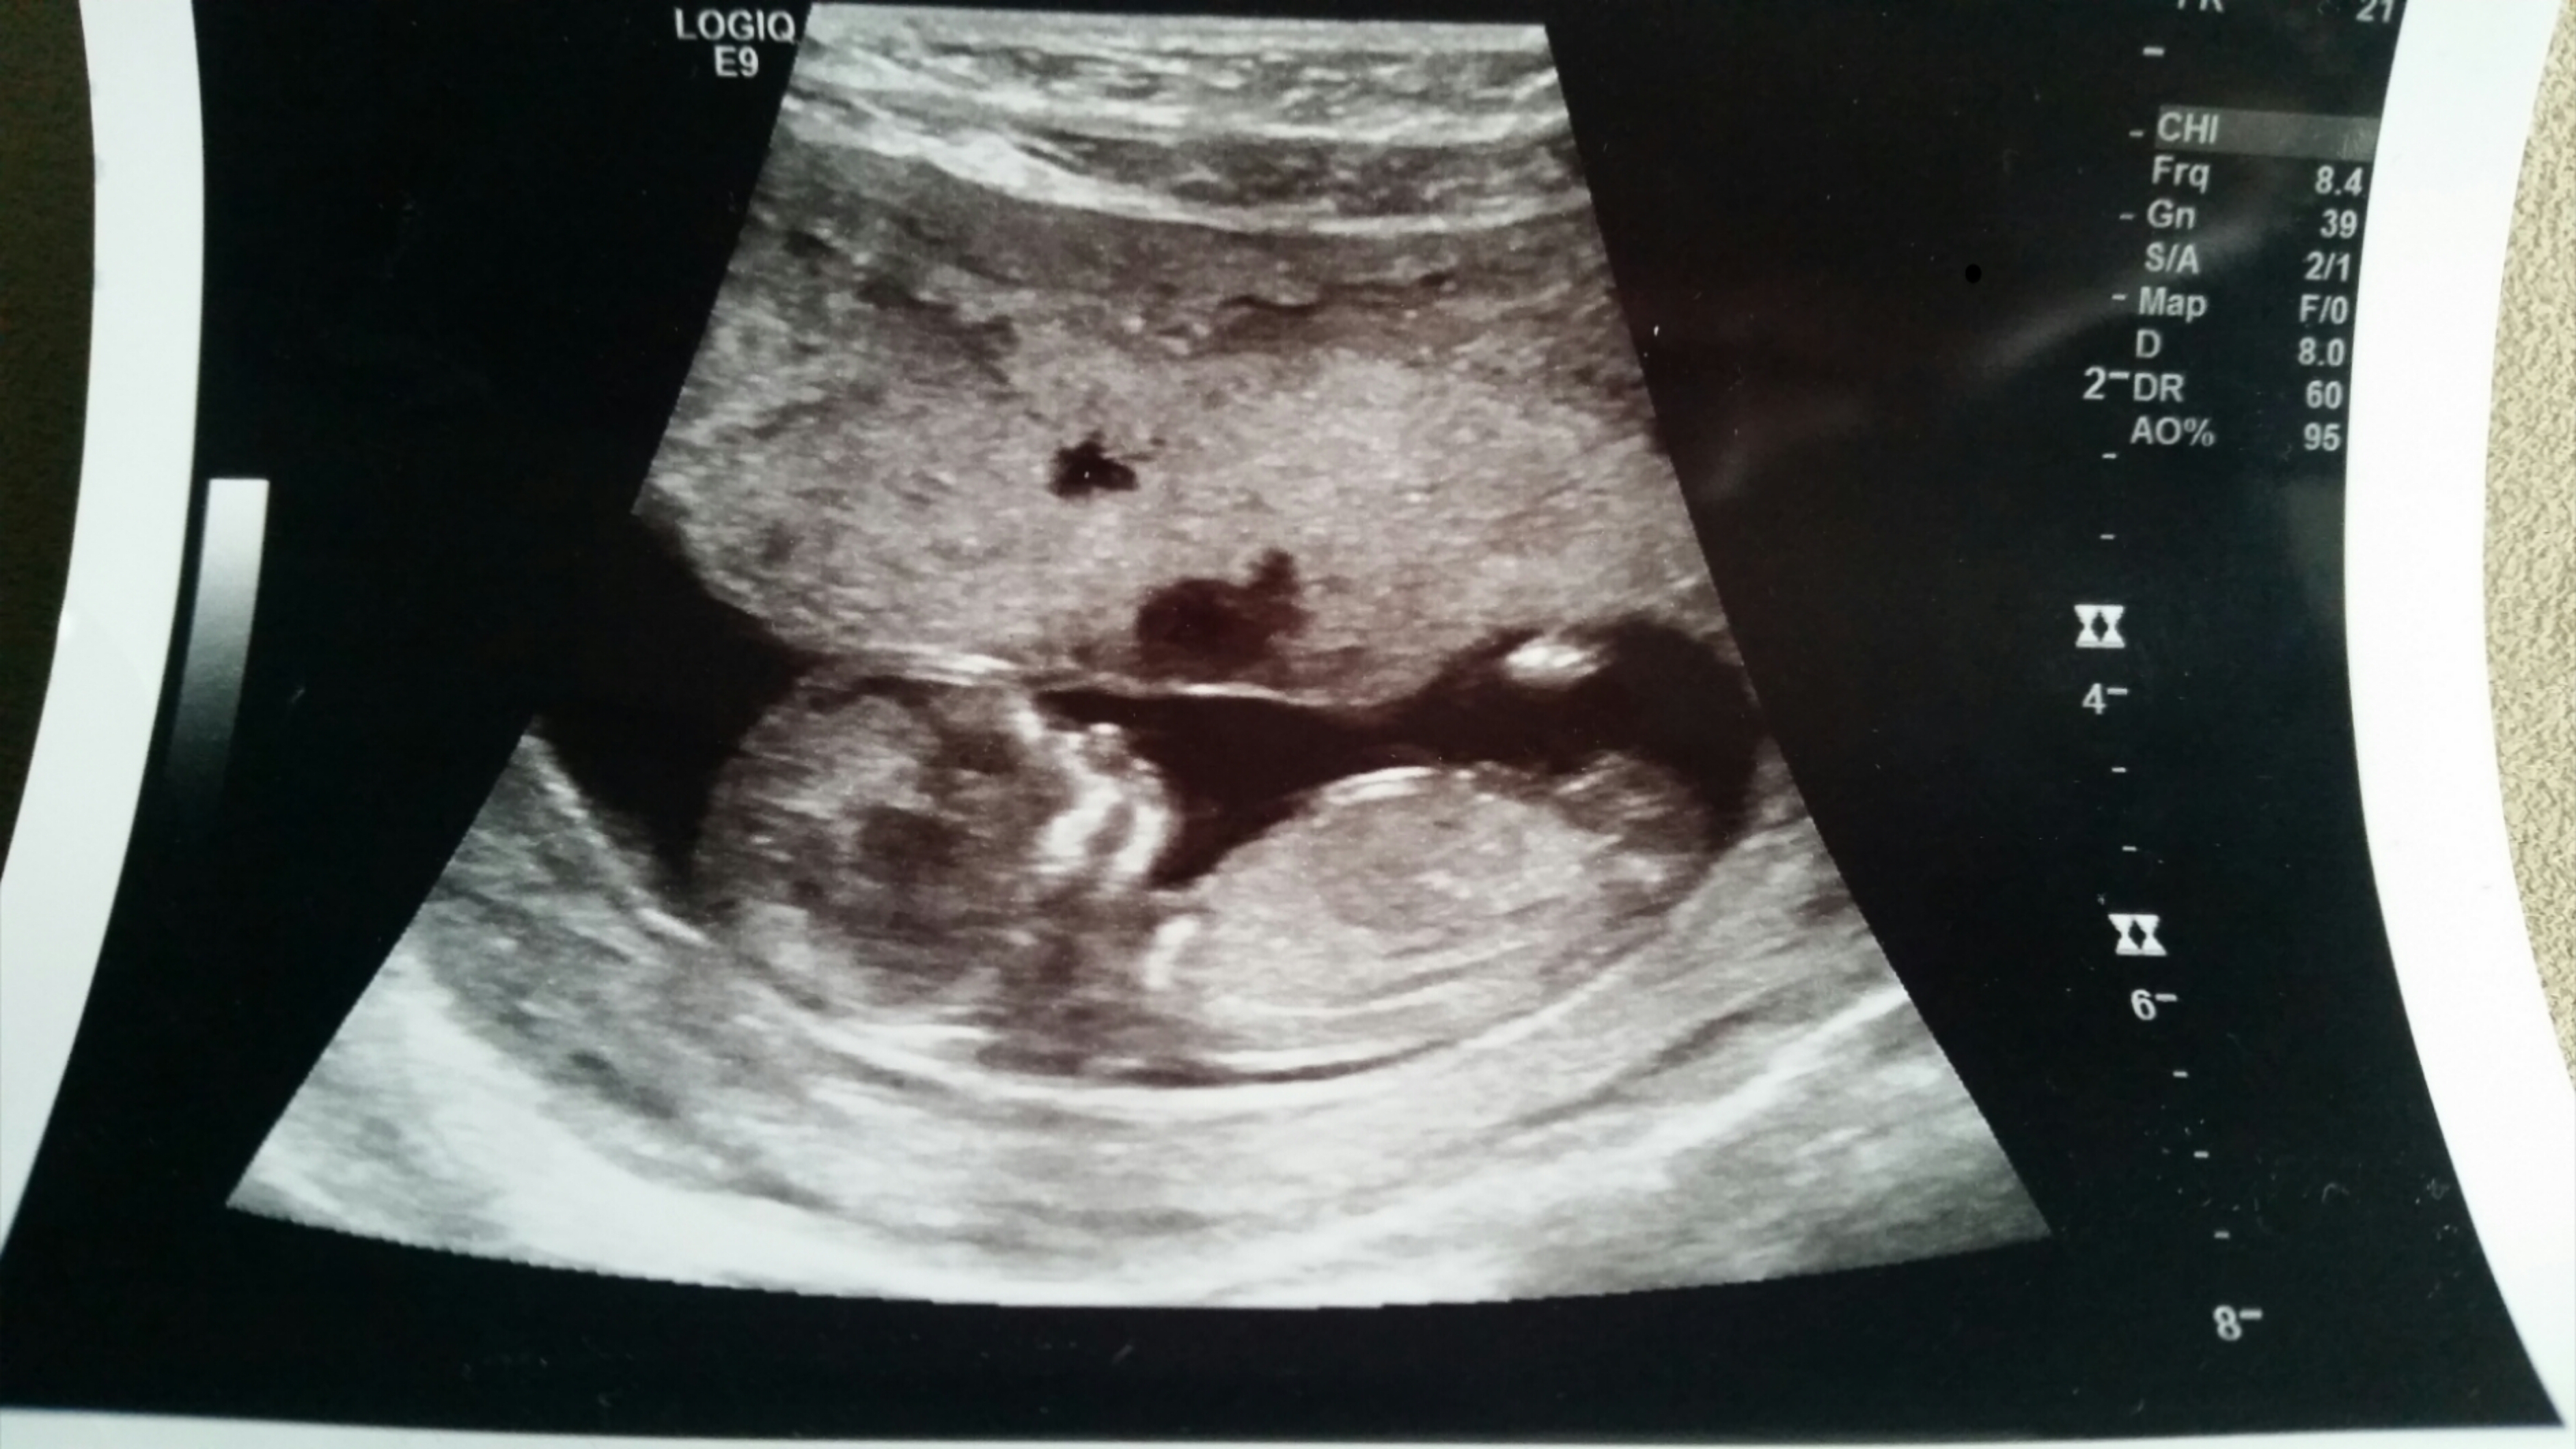

Skull theory or nub gender guesses please..

Attachment 31868

dont see a nub but skull looks boy x

Heres another shot.. can you see the nub?? Im not sure what to look for :/